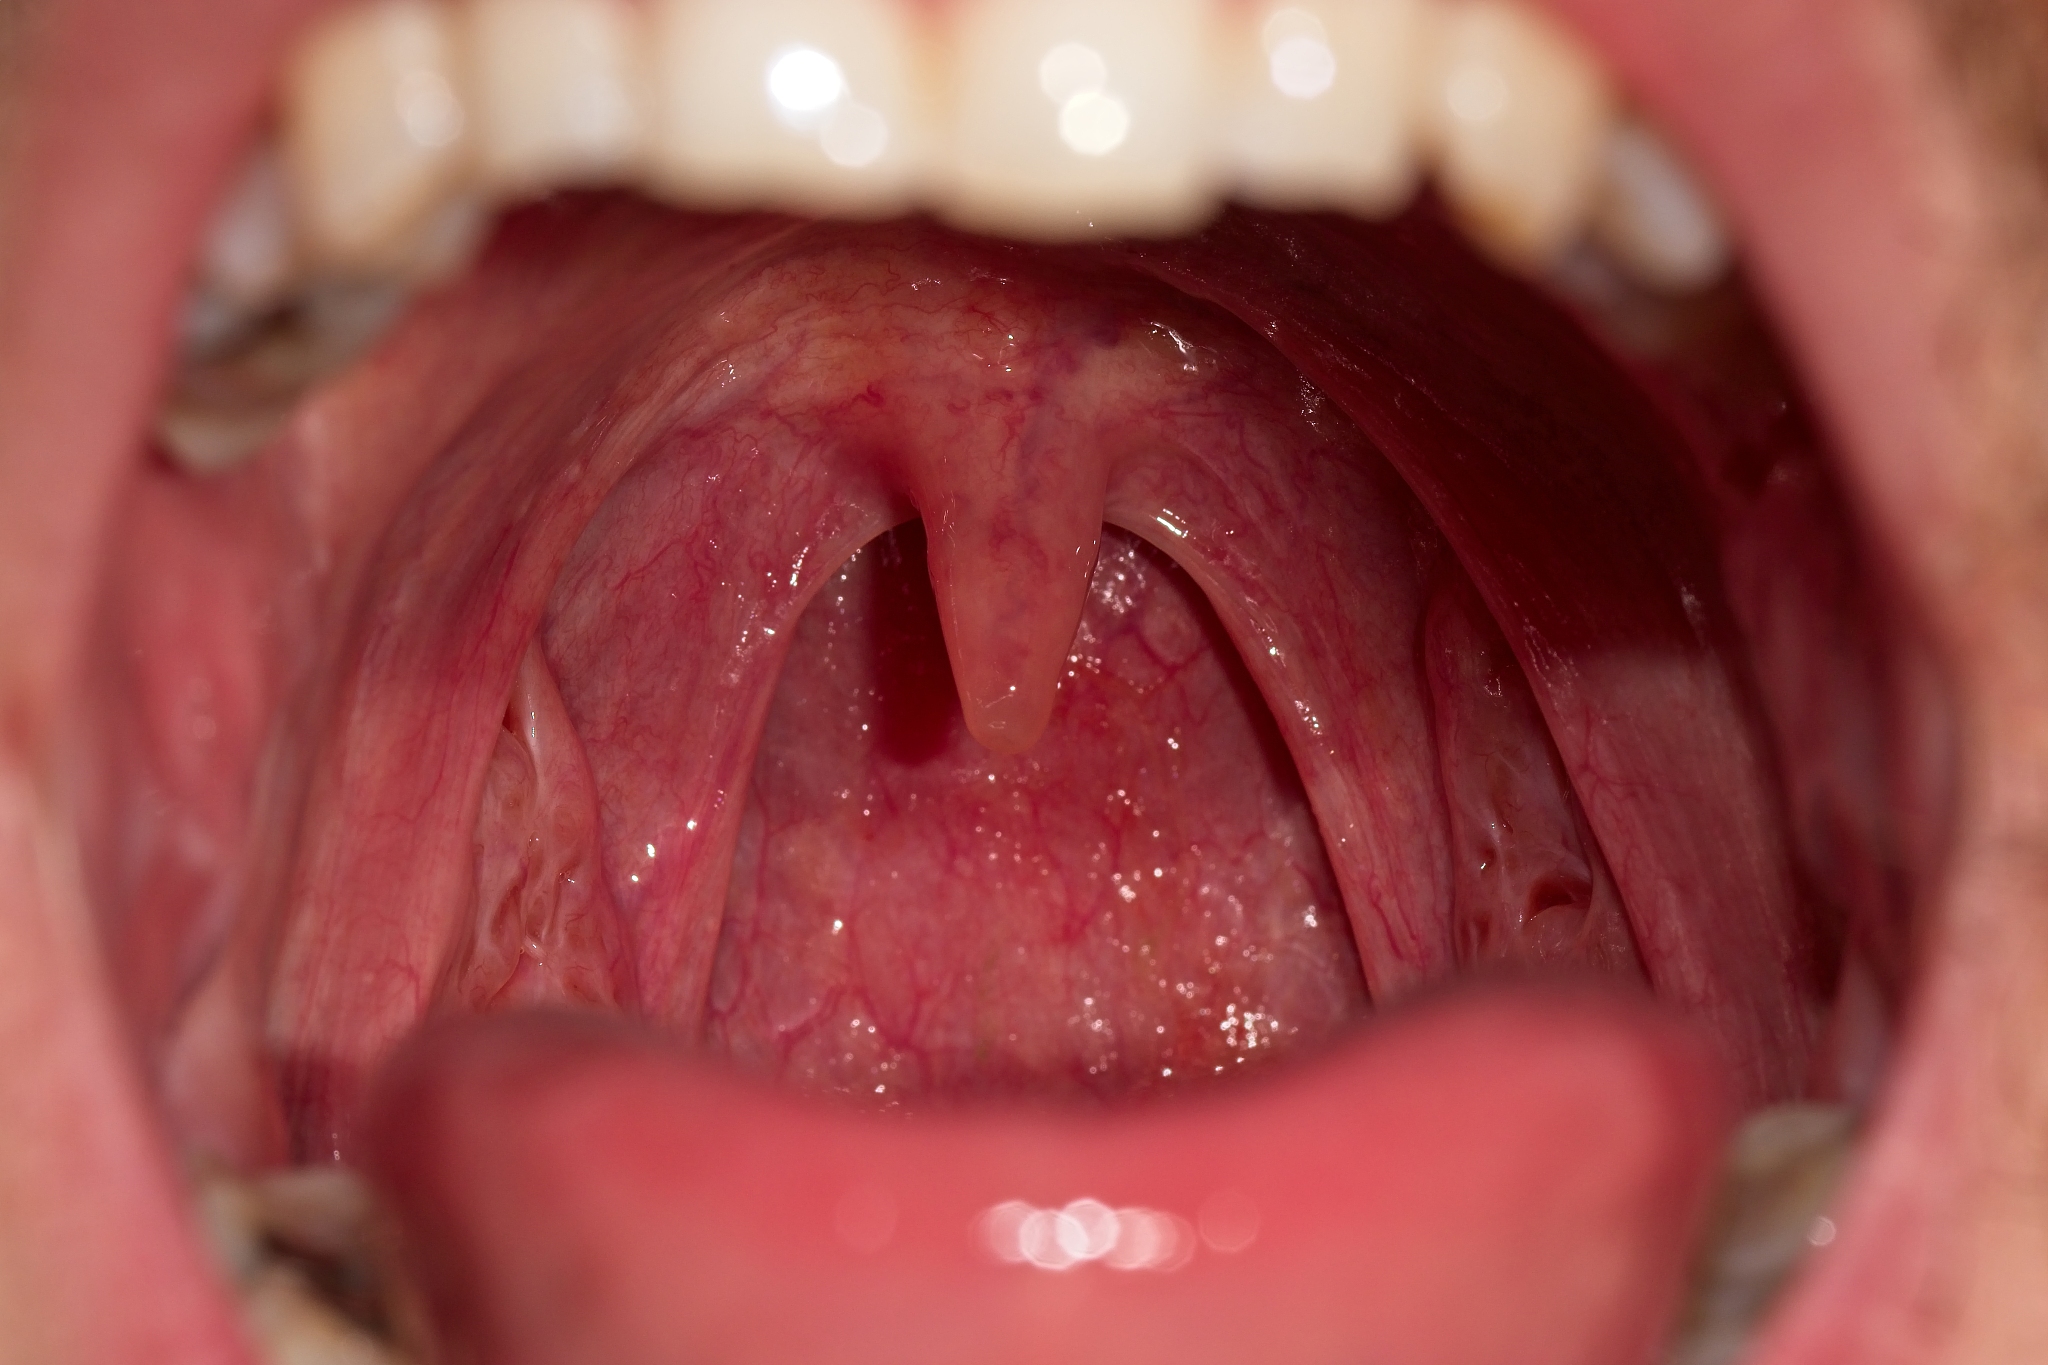

乐山卫生学校口腔医学专业是一门综合性学科,涉及口腔内科、口腔外科、口腔修复、口腔预防等多个方面。学生将在校内学习口腔解剖学、口腔生理学、口腔病理学、口腔微生物学等基础课程,同时还将接受口腔内科、口腔外科、口腔修复、口腔预防等临床课程的教育。

在校期间,学生将有机会参与临床实习,通过实践锻炼自己的临床技能和诊断能力。此外,学校还将组织学生参加各种口腔医学比赛和学术交流活动,拓宽学生的视野,提高学生的综合素质。